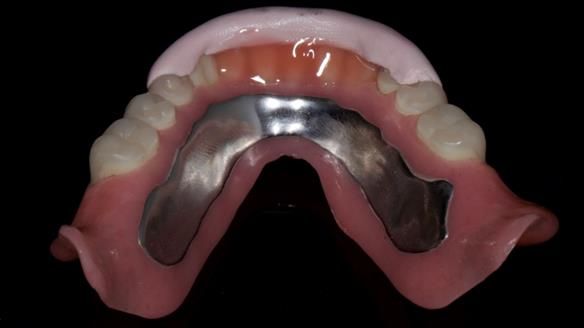

In this edition, I present the complete denture treatment for Kate, a 69-year-old American woman living in Garstang, UK. Kate had been edentulous for many years and required a set of complete dentures that closely mimicked her natural teeth. The new upper and lower dentures provided excellent retention and stability, with significant suction in the upper denture. Below, I detail the step-by-step process of her treatment, as well as my workflow for implant-supported overdentures for patients who may require them.

Treatment Process: I provided the clinical work while Rowan Garstang and Sam Hesketh delivered the technical aspects. The treatment required fifteen visits to fit and review Edgar.